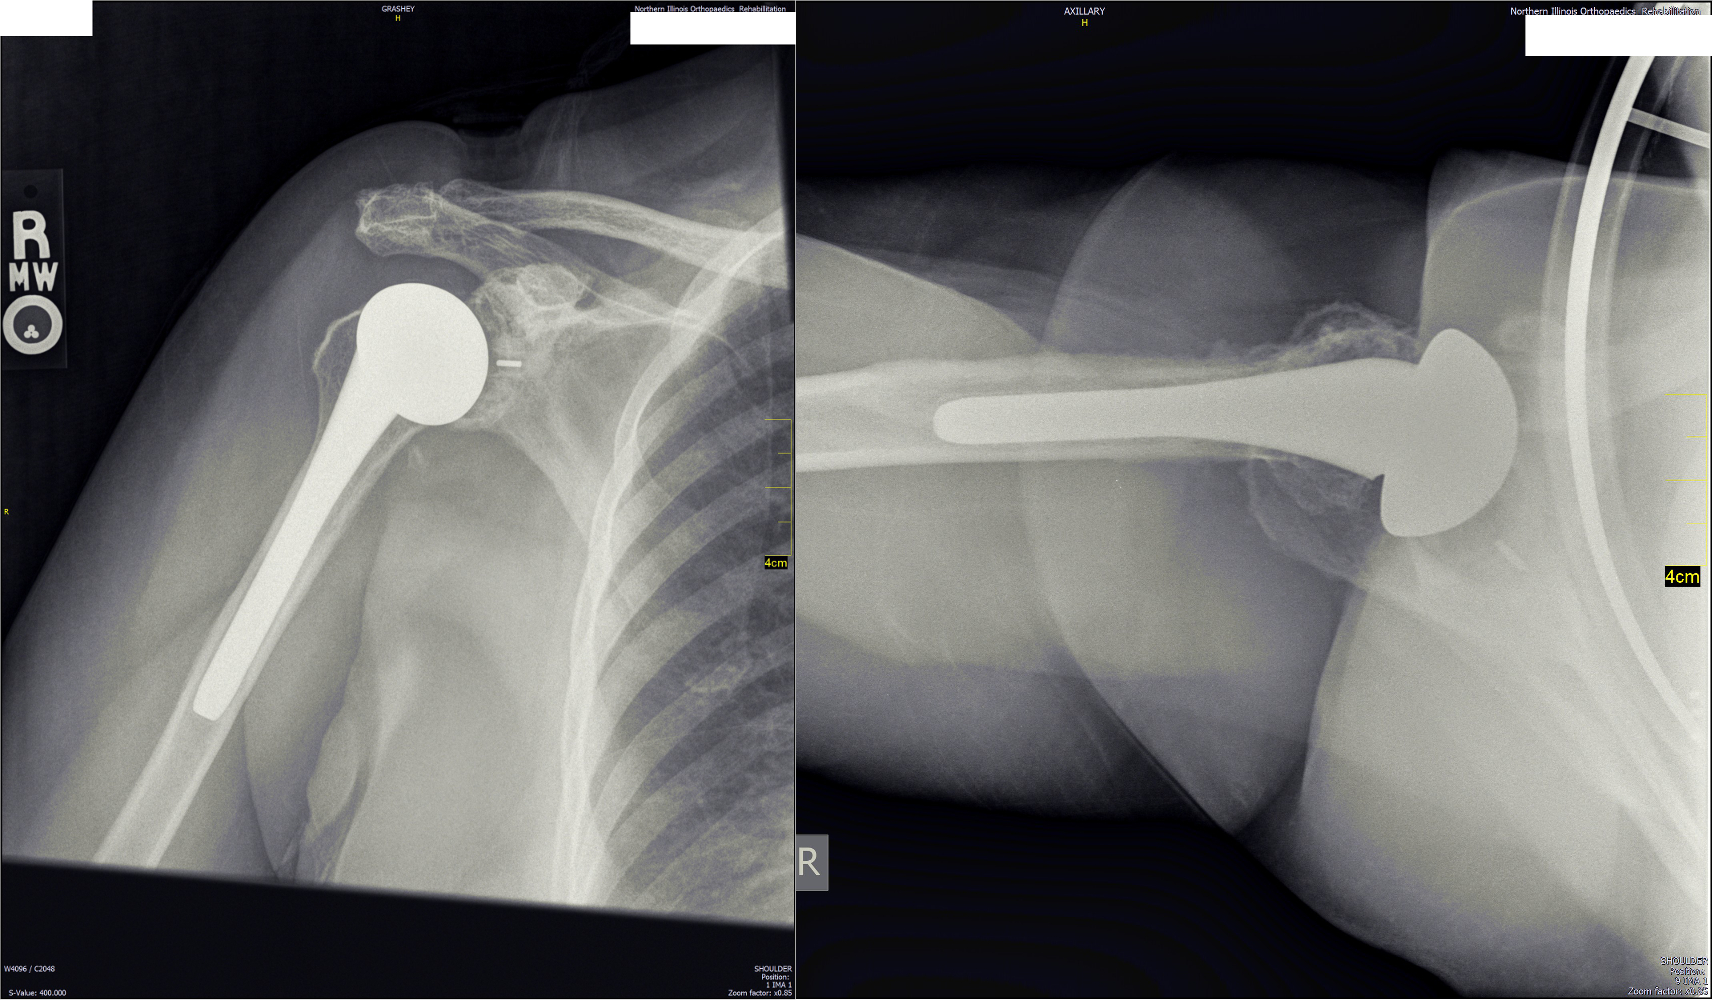

Below are xrays after surgery. This is a typical appearance of a shoulder replacement on xray. This is the same patient picture above, 3 years after her right shoulder replacement.

This prosthesis is the Exactech with a 38mm head.